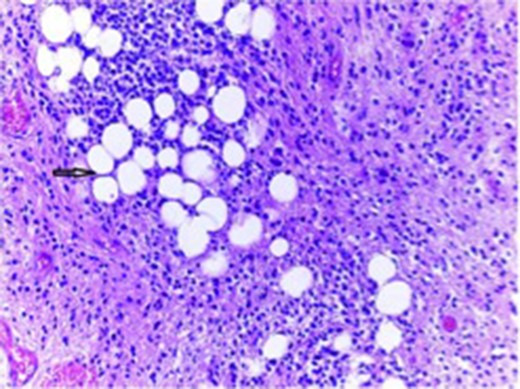

Tumor composed of uniform population of small neurocystic cells arranged in sheets and lobules and with regular round nuclei, clear cytoplasm. The histological hallmark of this entity is the focal accumulation of lipid-laden cells that resemble adipocytes (arrow).